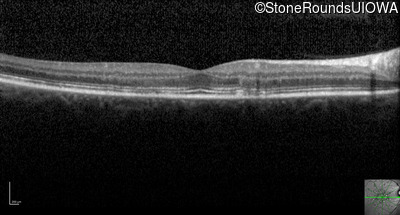

Optical Coherence Tomography - Right - 20/15

Exemplar / OCT Stack

OCT Stack